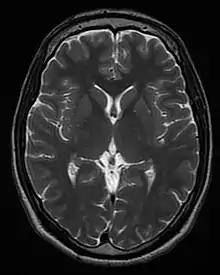

Image contrast and contrast enhancement

Image contrast is created by differences in the strength of the NMR signal recovered from different locations within the sample. This depends upon the relative density of excited nuclei (usually water protons), on differences in relaxation times (T1, T2, and T*

2) of those nuclei after the pulse sequence, and often on other parameters discussed under specialized MR scans. Contrast in most MR images is actually a mixture of all these effects, but careful design of the imaging pulse sequence allows one contrast mechanism to be emphasized while the others are minimized. The ability to choose different contrast mechanisms gives MRI tremendous flexibility. In the brain, T1-weighting causes the nerve connections of white matter to appear white, and the congregations of neurons of gray matter to appear gray, while cerebrospinal fluid (CSF) appears dark. The contrast of white matter, gray matter and cerebrospinal fluid is reversed using T2 or T*

2 imaging, whereas proton-density-weighted imaging provides little contrast in healthy subjects. Additionally, functional parameters such as cerebral blood flow (CBF), cerebral blood volume (CBV) or blood oxygenation can affect T1, T2, and T*

2 and so can be encoded with suitable pulse sequences.